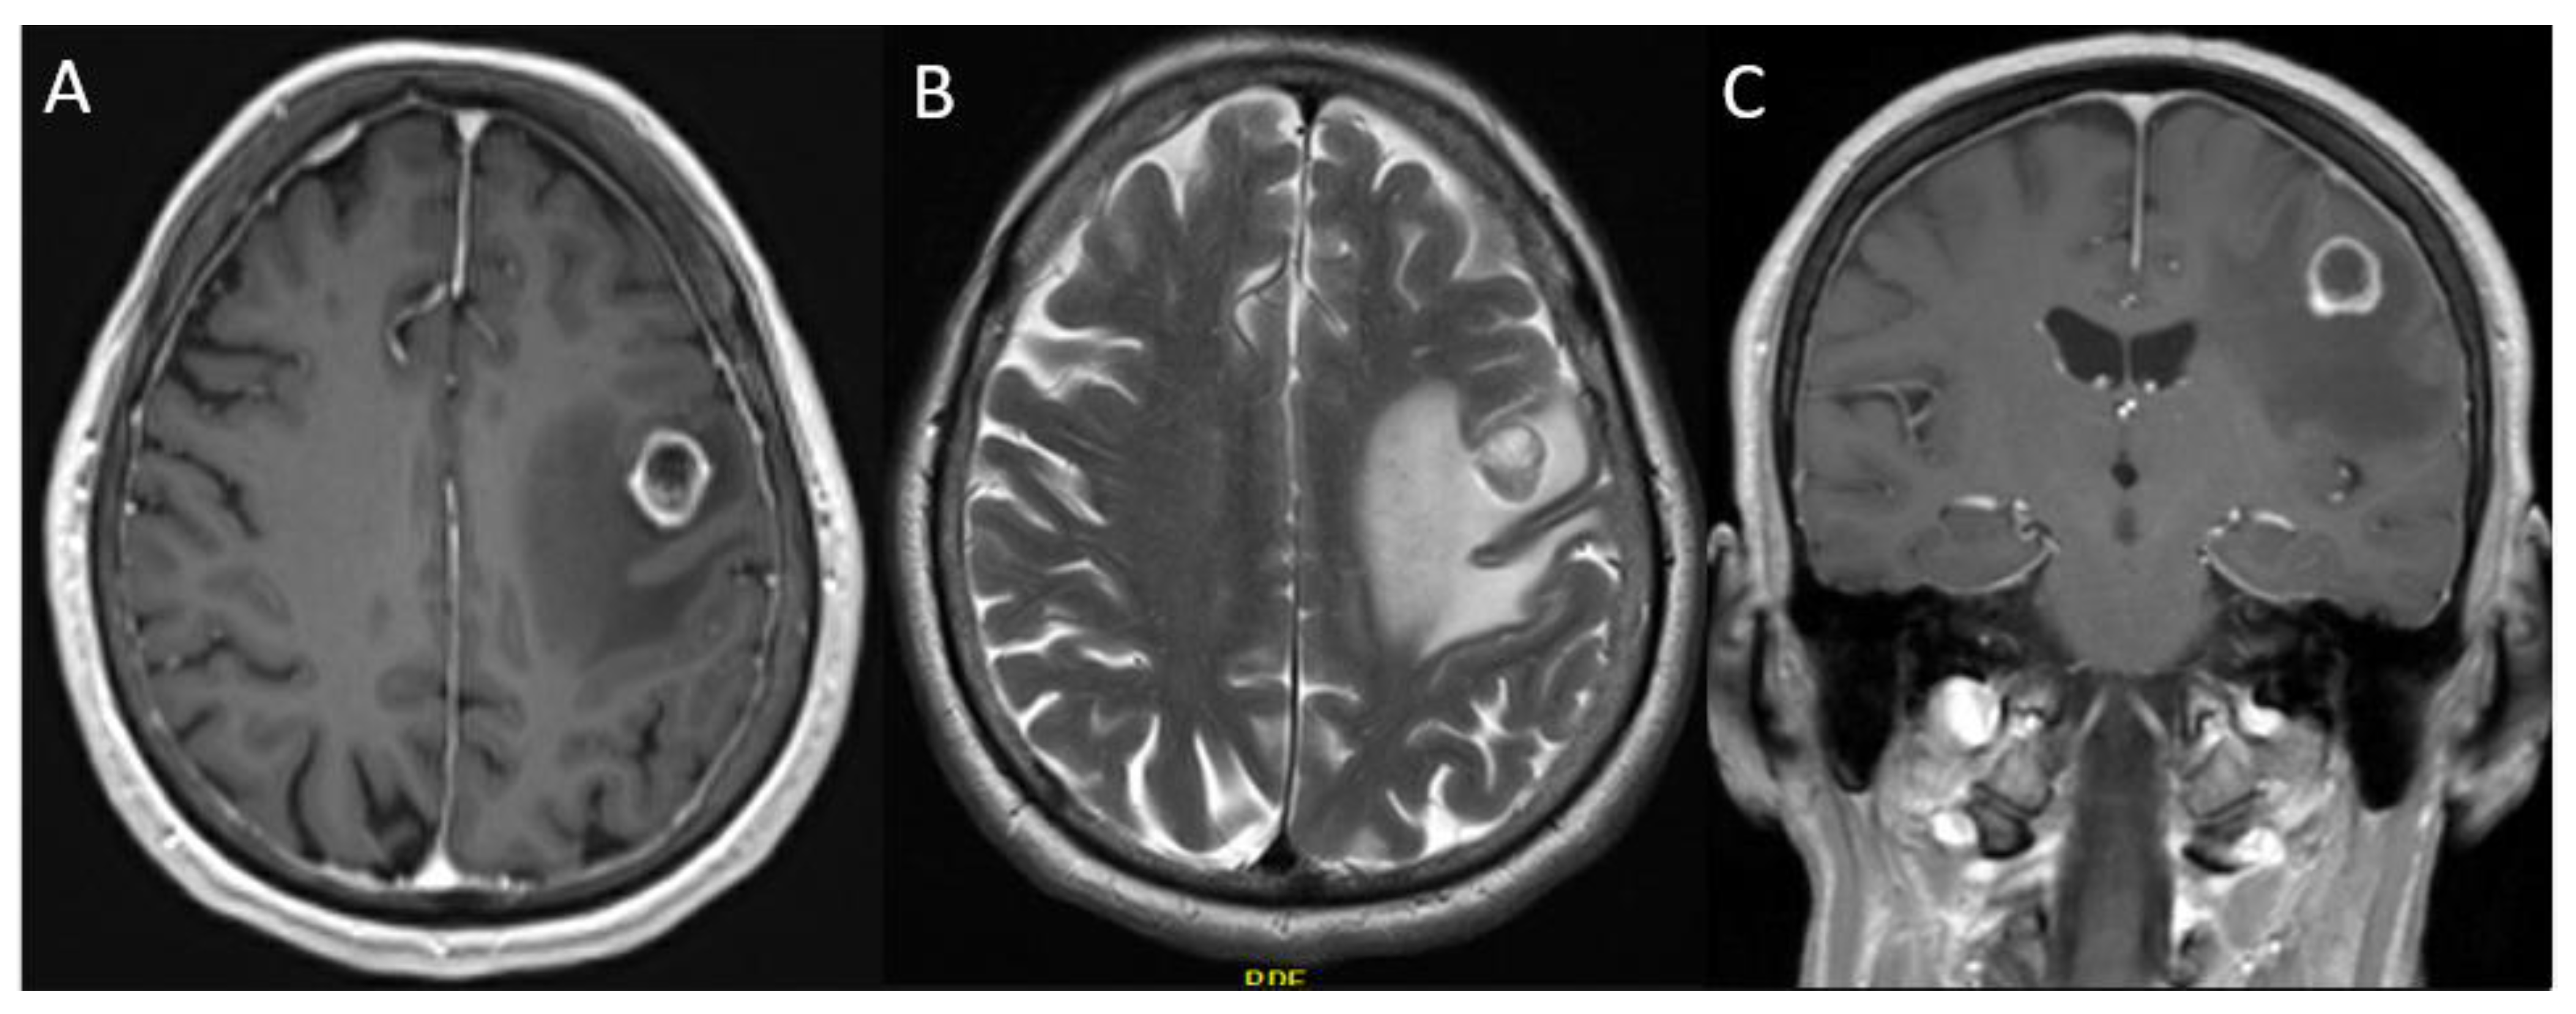

3.2.1. Case 1

3.2.2. Case 2